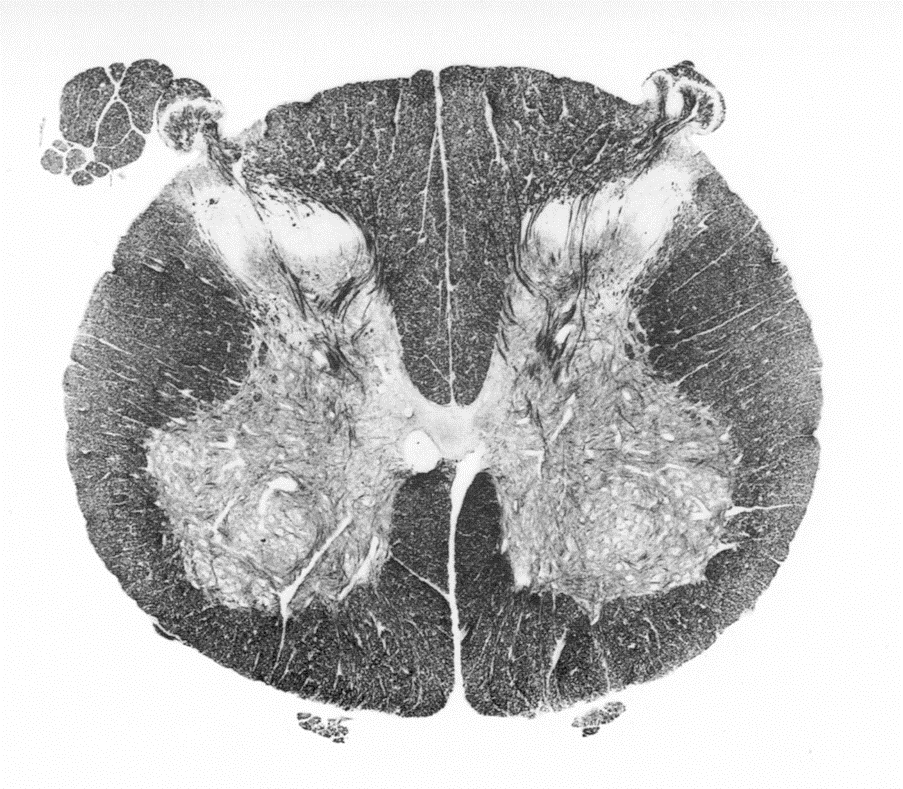

cervical region of spinal cord